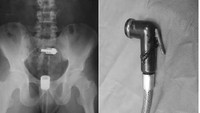

Selanjutnya adalah bidet. Seorang pasien pria berusia 29 tahun dilarikan ke rumah sakit karena bidet toiletnya menyangkut dalam anus untuk kepuasan seksual. Bidet itu berhasil dikeluarkan secara normal, dan pasien dikeluarkan dalam keadaan baik. (Foto: Malaysia Family Physician)